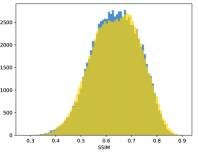

To visualise similarity metrics that compare image pairs (RMSE, SRE, SSIM) two metric distributions are generated: intra-similarity and inter-similarity. For each compared sample 300 random images are selected. The inter-similarity distribution is calculated for each image pair combination from both compared samples e.g. generated images of COVID-19 and real images of COVID-19. For the intra-similarity, all pairs of images in a single sample e.g real images of COVID-19 are considered. By comparing the shape of intra-similarity for the training subsample (Dataset) with the inter-similarity of training and generated samples the quality of the generated sample can be judged. It is also possible to compare in this way between the four image classes present in the dataset. The resulting distributions of inter-similarity of COVID-19 and the three remaining classes are compared in Fig. 4 to distributions of intra-similarity of the COVID-19 sample for each metric. All metrics, as expected based on available medical evidence Rubin et al. (2020), indicate that there are visible differences not only between COVID-19 and normal samples but also between viral pneumonia and lung opacity. Therefore, all classes should be distinguishable.

To visualise differences between synthetic and real samples distributions are generated for each of the RMSE, SRE and SSIM metrics: intra-similarity and inter-similarity. For each compared sample 300 random images are selected. The inter-similarity distribution is calculated for each image pair combination from both compared samples e.g. generated images of COVID-19 and real images of COVID-19. For the intra-similarity, all pairs of images in a single sample e.g real images of COVID-19 are considered. The distributions for generated samples describe very well the distributions for corresponding real images as shown in Fig. 6.

The quality of generated images is also confirmed with classical similarity metrics. The distributions of those similarity measures between generated and real images are compared for each sample with the distribution obtained within the real samples 6. The distributions for generated samples describe very well the distributions for corresponding real images. For an example see the results for the SSIM metric presented in Fig. 10. The small visible differences are almost insignificant compared to differences observed between the classes in Fig. 4.